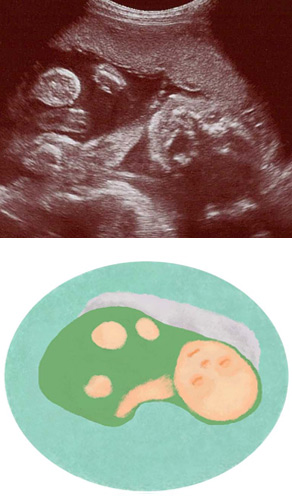

妊娠24週ころの超音波写真

赤ちゃんは自分で向きを変えられます

赤ちゃんは羊水の中で向きを変えて、さかごになったり戻ったりしています。へその緒の付着位置が中央寄りであると、赤ちゃんに十分な栄養が届きやすいでしょう。